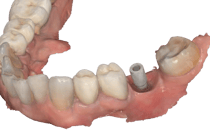

PRÓTESE SOBRE IMPLANTE UNITÁRIA E MÚLTIPLA

O fluxo digital na prótese sobre implante proporciona um avanço significativo em termos de precisão, estética e eficiência. Desde o escaneamento até a confecção final, cada etapa é otimizada para garantir resultados de alta qualidade e satisfação do paciente. Laboratórios qualificados e a integração de tecnologias de ponta são essenciais para alcançar resultados satisfatórios.

Escaneamento da gengiva e posição do implante

Desenho Digital em Laboratório

Coroa sobre Implante aparafusada em Modelo impresso. zirconia/cerâmica

Coroa instalada em boca